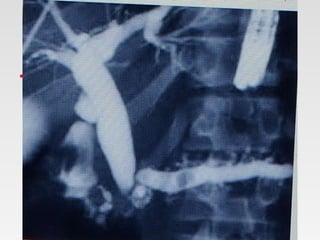

4-Imaging studies:

Abdominal x-ray:

Pancreatic calcifications, often considered

pathognomonic of chronic pancreatitis, are

observed in approximately 30% of cases.